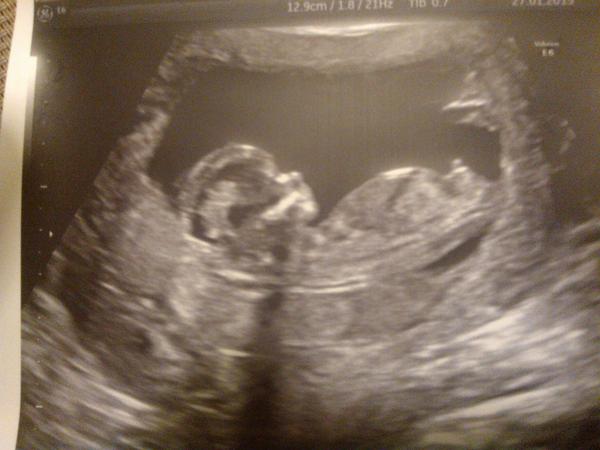

Ahoj @breberka82. Jak se zatím daří? Co miminko a co RS? Já včera byla na tom NT a všechno na jedničku. A k tomu nám jako bonus řekli, že to bude chlapeček 🙂 Mám radost. A RS pořád hezky spí 🙂

Posílám fotku a budu se těšit na tu tvou 🙂